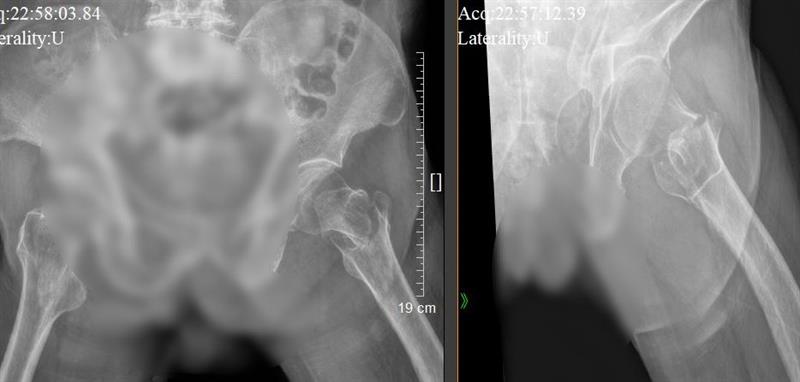

患者術前骨折X光片